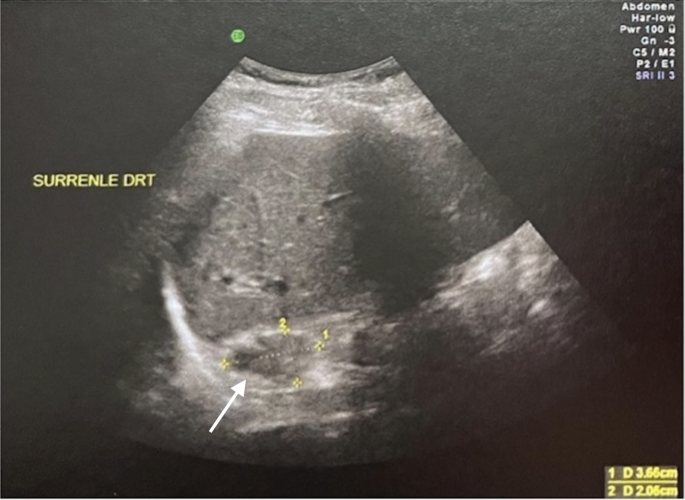

出院两个月后,随访超声显示左侧血肿消退,右侧血肿大小减小(20×36毫米对比28×42毫米)(图2)。患者继续接受替代治疗,并报告精力有所恢复。目前他为门诊患者,定期进行心脏病学和内分泌学检查。

两个月随访超声显示右侧肾上腺增大程度减轻,如箭头所示。大小从28×42毫米减小至20×36毫米